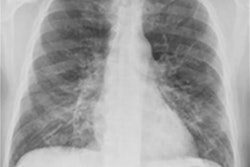

Researchers have developed a scoring tool for chest x-rays that can be used to predict outcomes for patients diagnosed with COVID-19, according to a study presented April 15 at the 2021 American Roentgen Ray Society (ARRS) virtual annual meeting.

The study identified laboratory, clinical, and radiographic data in chest x-rays that predicted important COVID-19 patient outcomes, such as death, intubation, and the need for chronic renal replacement therapy (CRRT). The tool was effective in settings of a high pretest probability of COVID-19 infection and can be used both at the attending chest radiologist and junior resident levels, according to the researchers.

"These findings are supported by prior work, validating the utility of [chest x-ray] for patient prognostication, while adding new insight into COVID-19 infection during the initial presentation," wrote the group led by Dr. Russell Reeves of Thomas Jefferson University in Philadelphia.

In the study presented at ARRS, Reeves and colleagues identified 240 patients (142 males, 98 females; median age, 65 years) with confirmed COVID-19 who were admitted to an urban multicenter health system from March 16 to April 13, 2020. Three cardiothoracic radiologists and three diagnostic radiology residents independently scored their admission chest x-rays, based on extent and severity of COVID-19 pneumonia. Demographic variables, clinical characteristics, and admission laboratory values were collected, while interrater reliability among attendings, residents, and the combined group of graders was assessed.

Reliability for the chest x-ray scoring was a mean of 0.686 among the attendings, residents, and combined group who used it. They identified no difference in outcomes across gender, race, ethnicity, or those with either a history of lung cancer or chronic obstructive pulmonary disease.

Although chest x-ray severity proved an independent predictor of death (p < 0.001), severity was a nonindependent predictor of CRRT (p = 0.007) and intubation (p < 0.001), but not extracorporeal membrane oxygenation, the authors concluded.